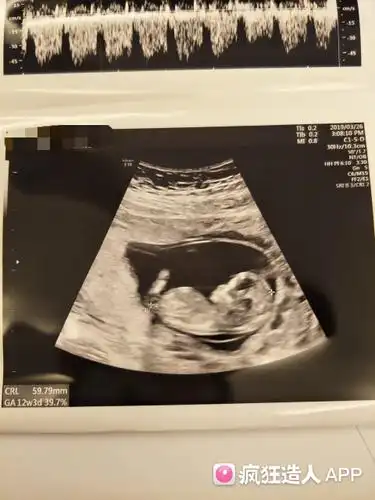

12周nt能看出男女嘛

可以看出男孩女孩吗?12周

12周nt顺利通过!感恩!